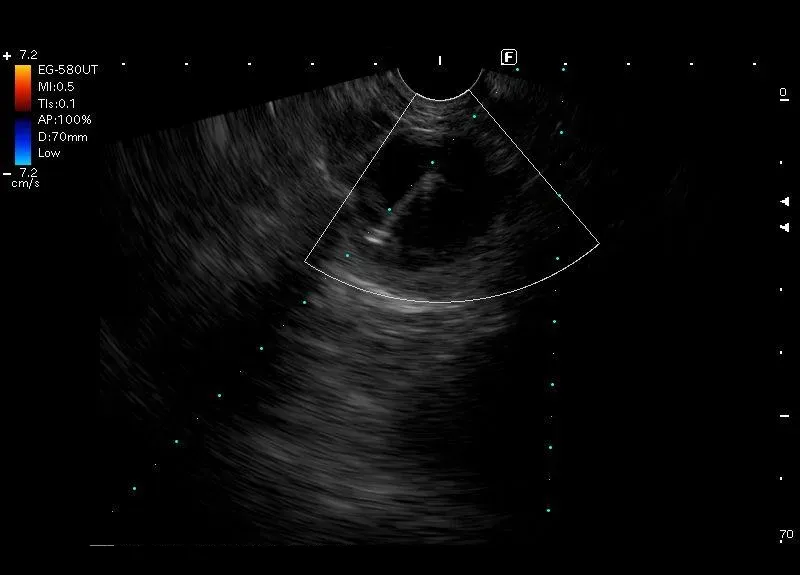

Biopsja zmiany o morfologii grubościennej torbieli ogona

trzustki z przyściennymi elementami litymi - widoczne jest echo igły i koniec

igły dochodzący do wewnętrznej ściany torbieli.